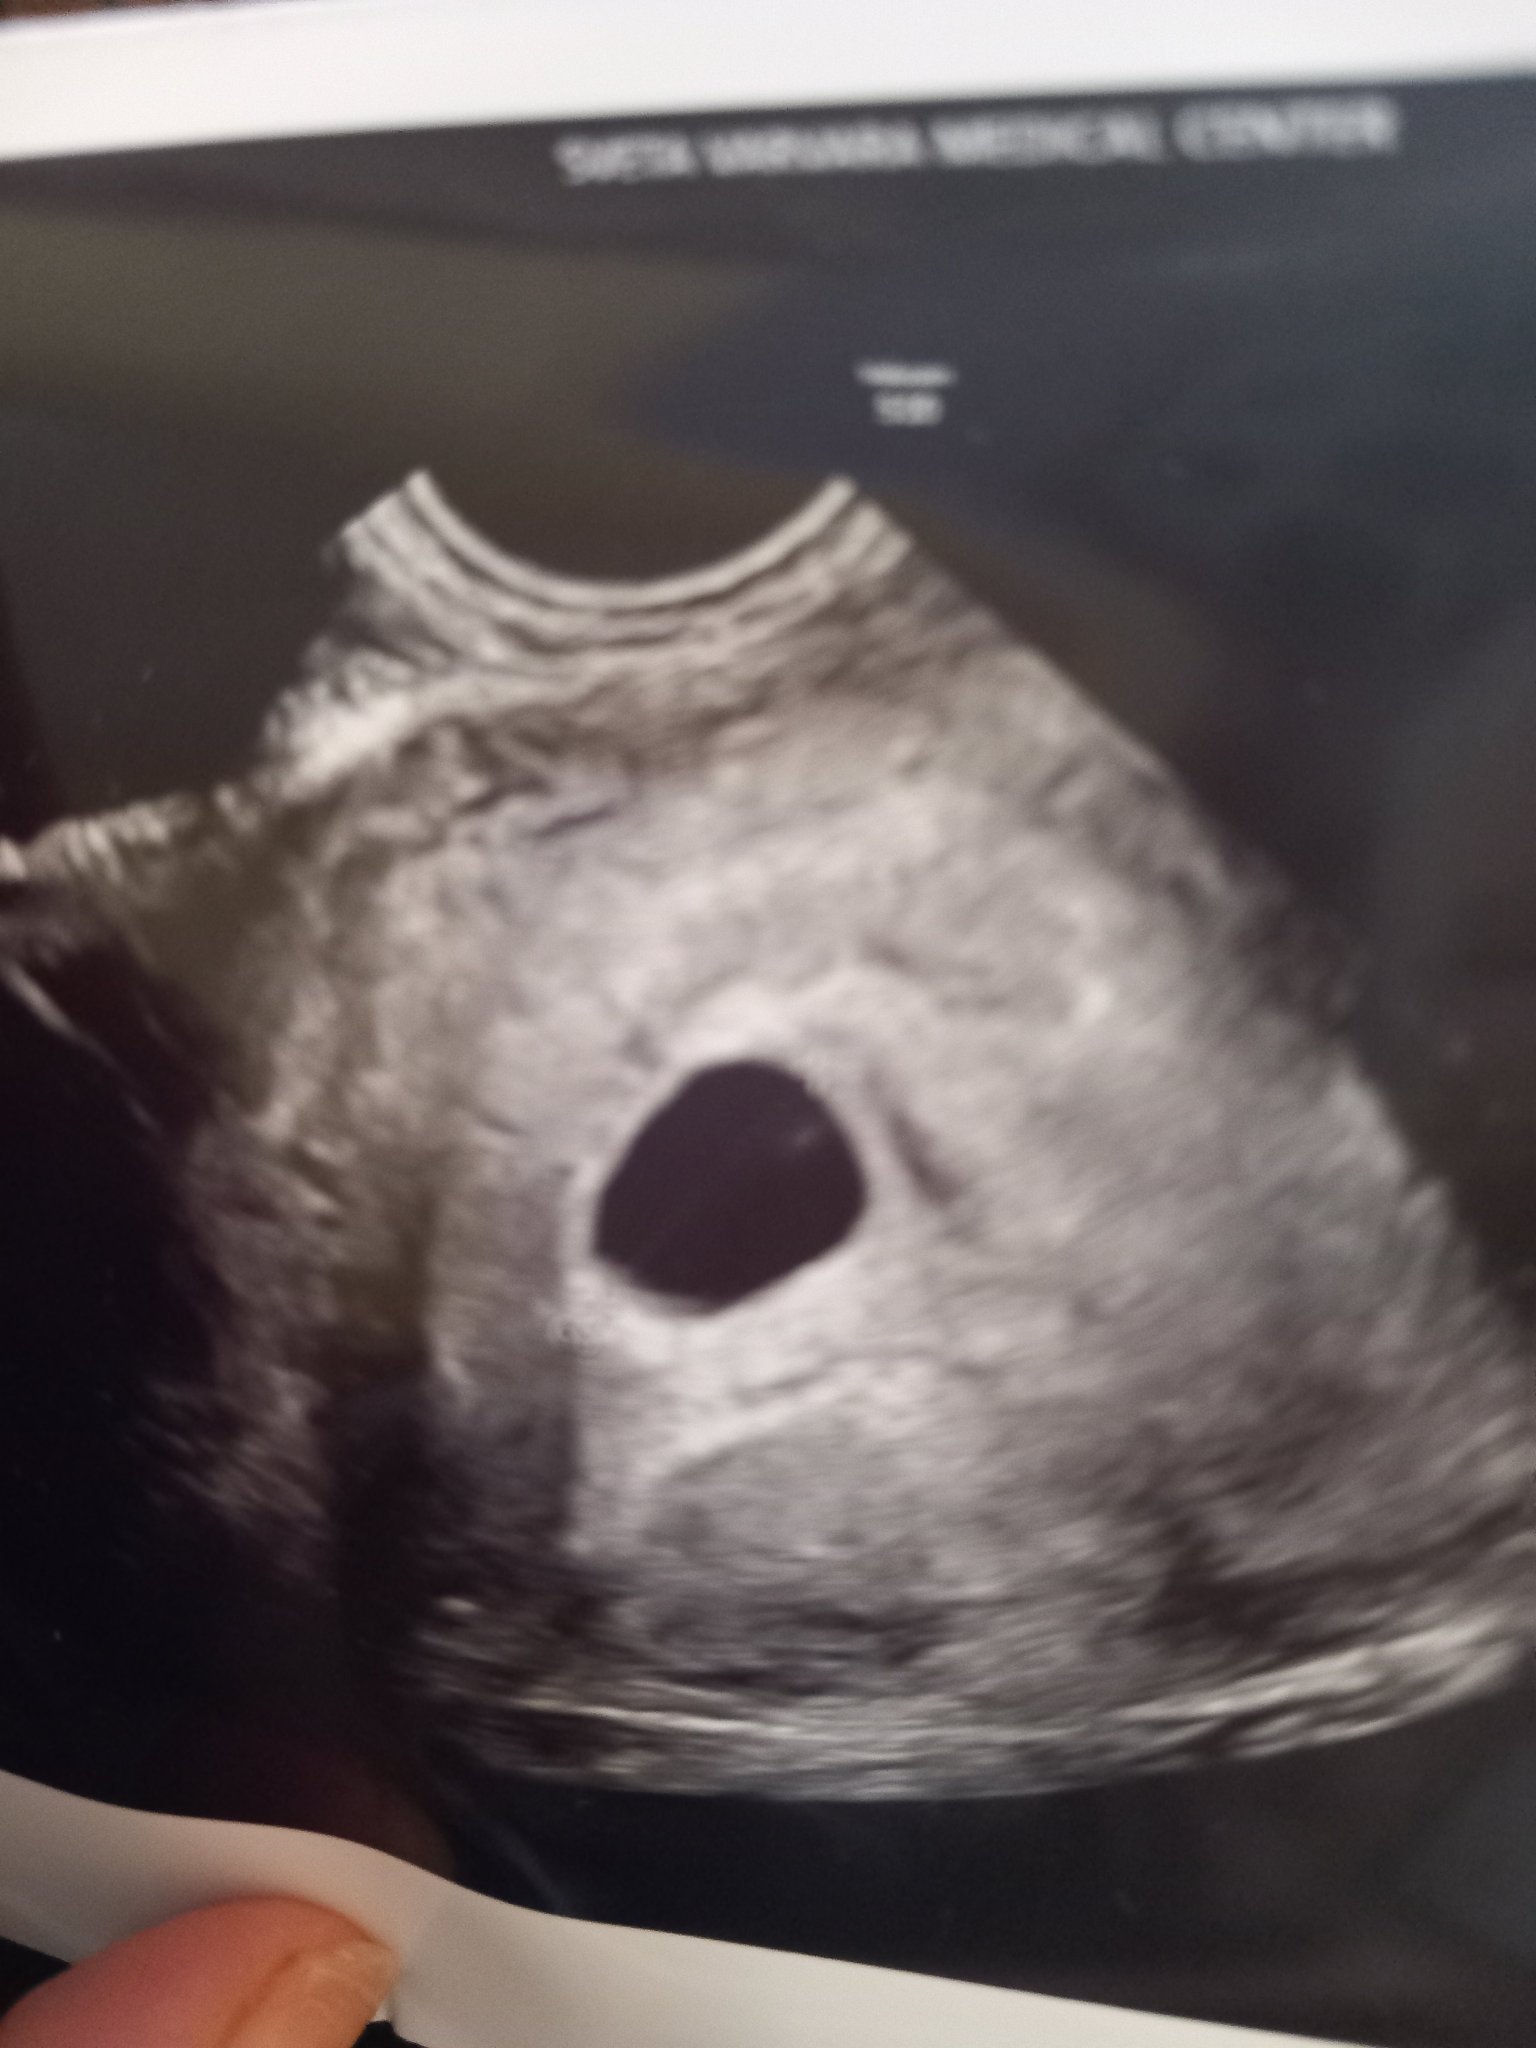

каза, че сакчето е по малко, качвам снимката от заключението й

Днес бях на преглед и доктора каза че по цикъл съм в 6.г.с.

А по плоден сак в 5г.с.

При мен каза че не вижда ембрион.

Каза че може да е рано!